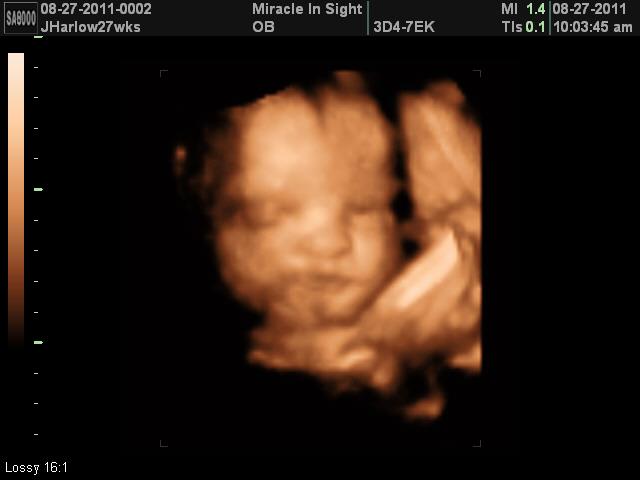

- You are never the same after the birth of your first child. Becoming a parent changes your life forever. The “perfect” parent becomes totally selfless at that point. I haven’t always been perfect, but my children’s needs became more important than mine.

- It’s worse after your first grandchild. You think having children changes your life? Having a grandchild increases that change 100 times over. As much as I love my kids, I absolutely adore my grandkids.